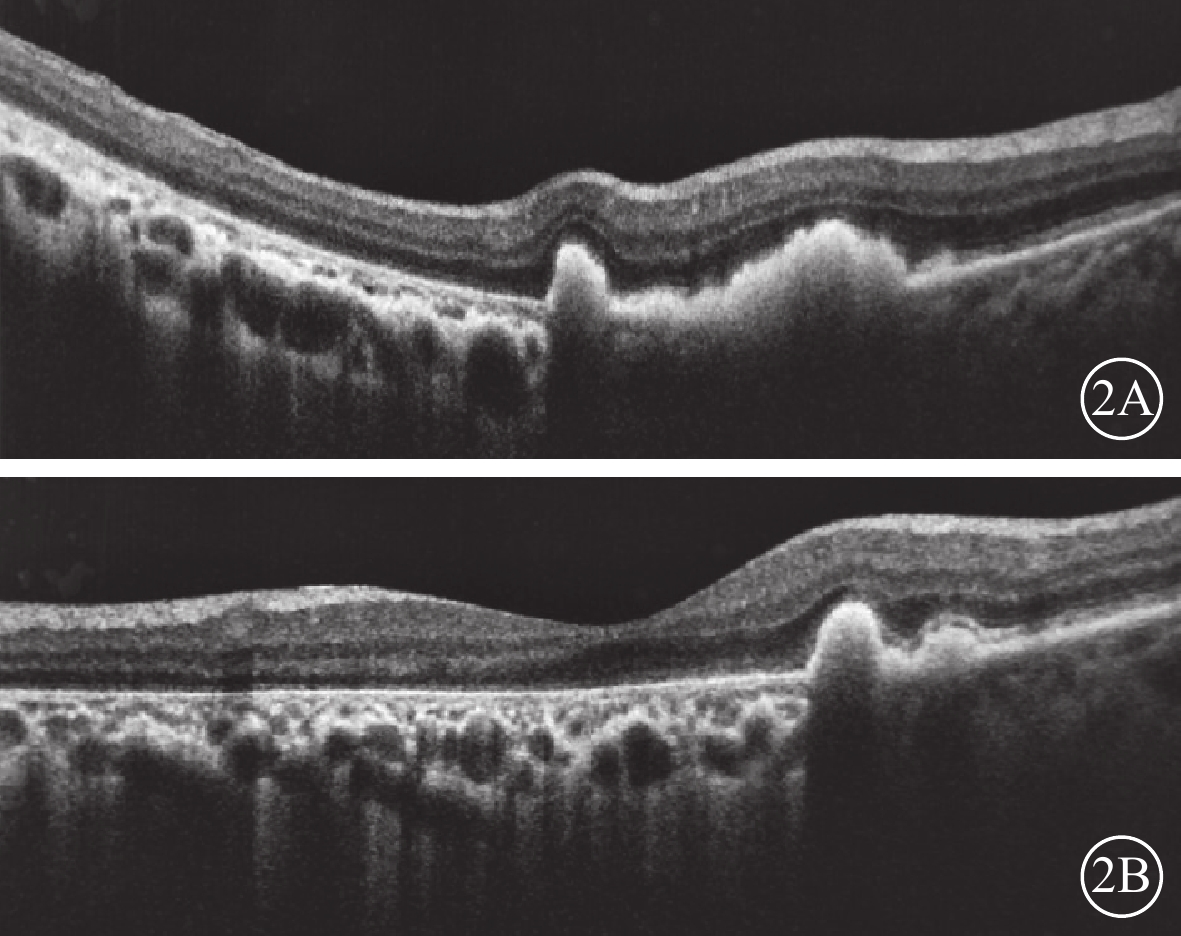

患者女,68歲。因雙眼視物模糊20 d于2018年3月20日來我院眼科就診。既往肺心病10年;否認雙眼外傷史,否認遺傳病家族史。眼部檢查:雙眼視力0.1,均不能矯正。右眼眼壓16 mmHg(1 mmHg=0.133 kPa),左眼眼壓15 mmHg。雙眼眼前節檢查正常。眼底檢查,雙眼后極部巨大RPE撕裂,撕裂區透見脈絡膜水腫;上方RPE收縮卷曲皺褶;視網膜血管紆曲(圖1)。OCT檢查,后極部撕裂區RPE信號消失。對應RPE卷曲皺褶處強反射隆起信號。未撕裂范圍RPE信號正常(圖2)。因患者原因未行FFA檢查。臨床診斷:雙眼特發性RPE撕裂。

圖2

雙眼OCT像。2A示右眼,卷曲的RPE呈隆起性強反射信號;2B示左眼,黃斑撕裂區RPE信號消失,脈絡膜水腫

圖2

雙眼OCT像。2A示右眼,卷曲的RPE呈隆起性強反射信號;2B示左眼,黃斑撕裂區RPE信號消失,脈絡膜水腫

患者女,68歲。因雙眼視物模糊20 d于2018年3月20日來我院眼科就診。既往肺心病10年;否認雙眼外傷史,否認遺傳病家族史。眼部檢查:雙眼視力0.1,均不能矯正。右眼眼壓16 mmHg(1 mmHg=0.133 kPa),左眼眼壓15 mmHg。雙眼眼前節檢查正常。眼底檢查,雙眼后極部巨大RPE撕裂,撕裂區透見脈絡膜水腫;上方RPE收縮卷曲皺褶;視網膜血管紆曲(圖1)。OCT檢查,后極部撕裂區RPE信號消失。對應RPE卷曲皺褶處強反射隆起信號。未撕裂范圍RPE信號正常(圖2)。因患者原因未行FFA檢查。臨床診斷:雙眼特發性RPE撕裂。

圖2

雙眼OCT像。2A示右眼,卷曲的RPE呈隆起性強反射信號;2B示左眼,黃斑撕裂區RPE信號消失,脈絡膜水腫

圖2

雙眼OCT像。2A示右眼,卷曲的RPE呈隆起性強反射信號;2B示左眼,黃斑撕裂區RPE信號消失,脈絡膜水腫